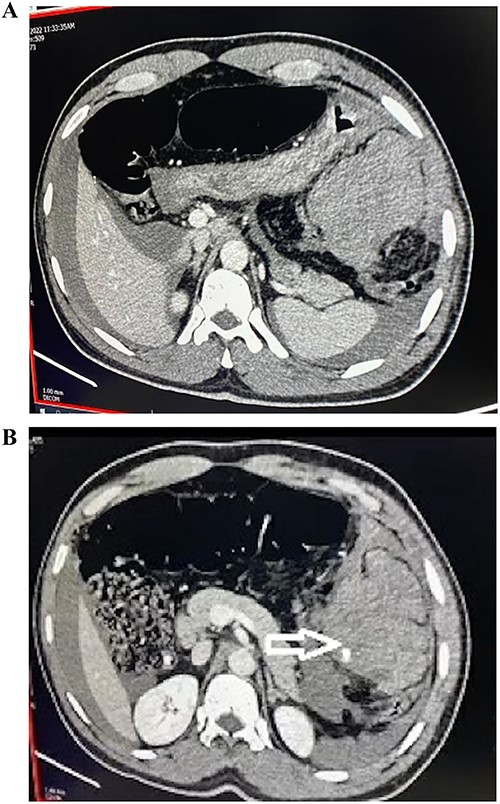

On further confirmation with contrast-enhanced computed tomography (CT) scan, it revealed hyperdense area of blood density, suggestive of hematoma, with eccentric focal intrinsic extravasation of contrast in the left hypochondrium—likely omental bleed (Fig. 1). Due to spontaneous hemoperitoneum, tachycardia and anemia—the patient was subjected to emergency laparotomy. At surgery, 2 l of intraperitoneal blood was suctioned. There was a large hematoma of size 10 by 12 cm noted in the left half of the greater omentum along the splenic flexure. Active ooze of blood from the greater omentum was noticed. Hence, greater omentectomy (partial) was done to control bleeding. No other solid organ injury or vessel aneurysm was identified.

(A, B) CT abdomen and pelvis with IV contrast demonstrating hyperdense area of blood density suggestive of hematoma with eccentric focal intrinsic extravasation of contrast at left hypochondrium.